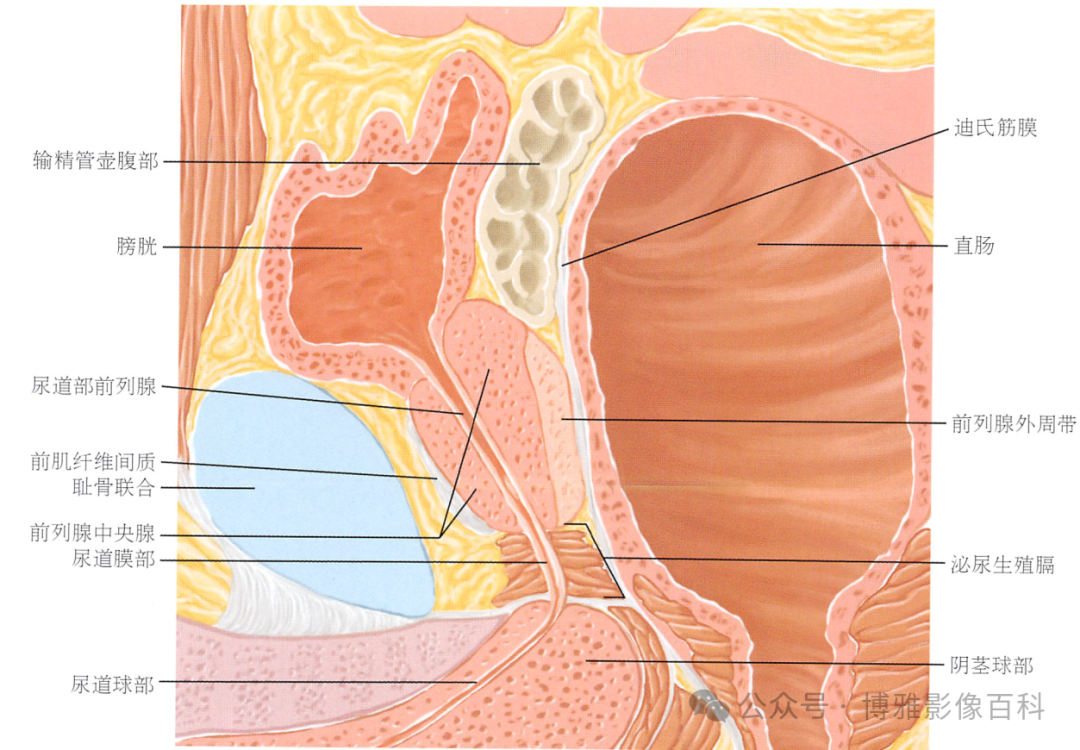

解剖学

前列腺分区解剖学

MR 解剖学